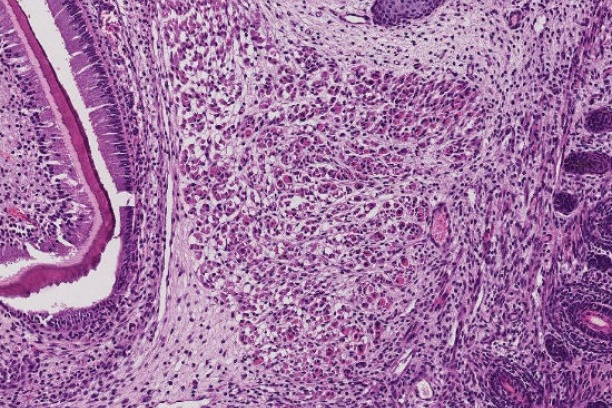

The Digital Histology Shared Resource provides large-scale digital archiving and quantitative analysis of histologic, immunohistochemical and immunofluorescence staining of tissue sections and tissue microarrays. Two Aperio Versa automated scanning microscopes, and Aperio AT2 and a Leica SCN400 Slide Scanner deliver solutions for high-resolution imaging in both bright field and fluorescence. All instruments have high-capacity robotic autoloading (200 slides for the Aperio Versa and Aperio AT2 and 384 slides for the Leica SCN400) making them ideal for large slide cohorts and tissue microarrays. The associated software packages provide complex algorithms for unbiased, automated image analysis and quantitation of immunostaining in both bright field and fluorescence. In addition, these systems can be utilized as a permanent high-resolution solution for those who need archiving of histologic material. The DHSR hosts a convenient, web-based digital slide-viewing environment (Digital Slide Archive) for the rapid retrieval, review, annotation and image acquisition of scanned material. This easy to use digital slide box allows researchers to share images among colleagues from any web browser while remaining in a digitally secure environment. Expert assistance is offered in planning experiments and processing data in a consistent, objective, and timely manner. The automated imaging and analysis performed in this core saves researchers and staff weeks of tedious work. An additional service offered by the DHSR is the creation of digital archives of critical and irreplaceable tissue samples, a benefit only feasible due to the automated high-resolution imaging of whole 25 mm x 75 mm microscope slides and 50 mm x 75 mm "double" slides.